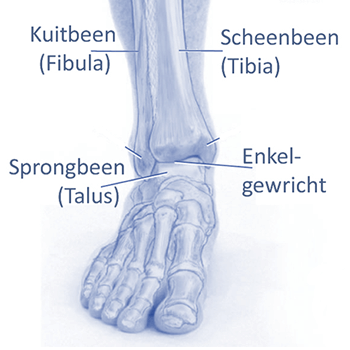

Enkelklachten zijn klachten die men ervaart in en/of rondom het enkelgewricht. Dit gewricht bestaat uit drie botstukken: het scheenbeen (tibia), het kuitbeen (fibula) en het sprongbeen (talus). De enkel wordt verstevigd door een gewrichtskapsel, pezen en meerdere enkelbanden. Deze lopen langs de binnen- en buitenkant van het gewricht. De gewrichtsbanden worden ook wel ligamenten genoemd.